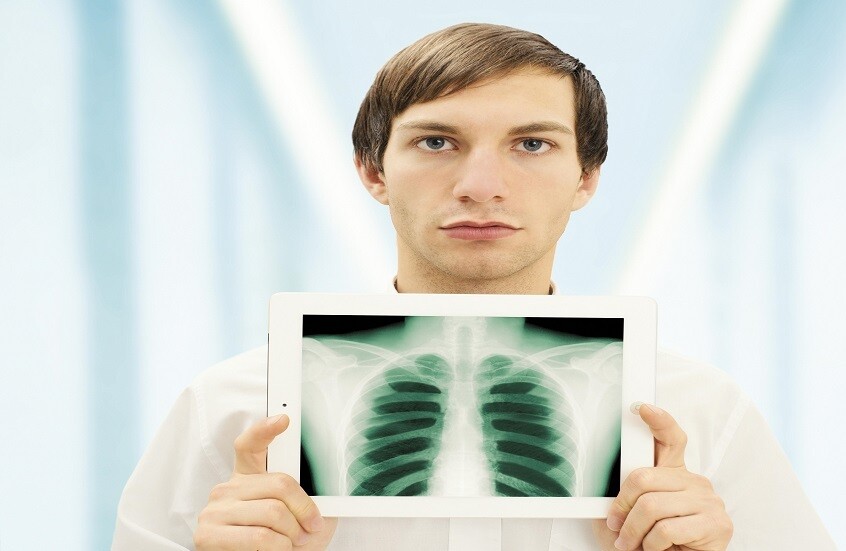

ما مدى خطورة الأشعة السينية على الصحة؟

أفادت الدكتورة أوكسانا بلاتونوفا أخصائية الأشعة، أن الأشعة السينية لا تزال أداة تشخيصية مهمة، ولكن لا تزال المخاوف تحيط بها.

وتوضح الطبيبة، لماذا قد يكون رفض الفحص أكثر خطورة على الشخص من الإشعاع نفسه.

ووفقا لها، يستخدم الإشعاع فقط في أنواع معينة من الفحوصات، ولا تتضمن جميع طرق التشخيص التعرض للإشعاع. فمثلا، يستخدم التصوير بالموجات فوق الصوتية والتصوير بالرنين المغناطيسي وهذه طرق آمنة تماما حتى للنساء الحوامل. أما الأشعة السينية فتستخدم فقط في التصوير الشعاعي، والتصوير الفلوري، والتصوير المقطعي المحوسب، بينما لا تتضمن طرق أخرى التعرض للإشعاع.

وتقول: "يمكن للنساء المرضعات الخضوع لأشعة الأسنان السينية، والتصوير الفلوري، وتصوير الثدي بالأشعة السينية بأمان. ولا يؤثر الإشعاع على حليب الثدي أو الطفل. ولكن توصف الأشعة السينية للنساء الحوامل فقط في حالات طبية صارمة، وحينها يجب حماية البطن بمئزر من الرصاص".

وبالإضافة إلى ذلك، تصدر الأجهزة الحديثة جرعات ضئيلة. أي لتلقي الإشعاع الضار، يتطلب الأمر الخضوع لمئات عمليات المسح المتتالية - وهو أمر مستحيل في الممارسة العملية. وللمقارنة، تصدر أشعة الأسنان السينية حوالي 30 ميكروسيفرت، وتصدر أشعة الفلوروغرافي (fluorography) حوالي 500 ميكروسيفرت، و تعتبر الجرعة التي تزيد عن 50 ألف ميكروسيفرت سنويا خطيرة.

الأشعة السينية تكشف عن الفرق الهائل الذي تحدثه لقاحات "كوفيد-19" حقا في الرئتين

وتشير الطبيبة إلى أنه لا أساس من الصحة للمخاوف الشائعة بشأن مخاطر أشعة الأسنان السينية. لأن الشعاع يركز بدقة على المنطقة المطلوبة، وتغطى الأنسجة المحيطة به.

وتقول: "الأشعة السينية هي إشعاع كهرومغناطيسي، مثل الأشعة فوق البنفسجية والضوء والحرارة. صحيح قد تلحق جرعاتها العالية الضرر بالخلايا، كالذي تسببه حروق الشمس. وأن الاستلقاء تحت أشعة الشمس على الشاطئ دون حماية أخطر بكثير من تصوير بالأشعة السينية للصدر مرة واحدة سنويا".

وتؤكد بلاتونوفا، أن عدم اكتشاف المرض أخطر بكثير من الخضوع للأشعة السينية، حيث المعدات الحديثة تقلل من المخاطر، كما أن الفحوصات في الوقت المناسب تسمح بالكشف السريع عن الأمراض وبدء العلاج.

المصدر: صحيفة "إزفيستيا"